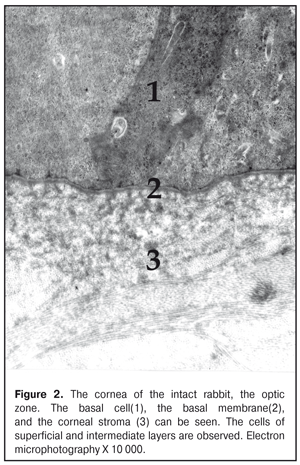

https://doi.org/10.31288/oftalmolzh201736369 Effect of colloidal silver nanoparticle solution instillation on the ultrastructure of the corneal epithelium and stroma V.A. Ulyanov, Prof., Dr. Sc. (Med.) 1 M.B. Makarova, a Postgraduate student, immunologist1, 2 N.I. Molchaniuk, Cand. Sc. (Biol.) 2 N.A. Ulyanova, Prof., Dr. Sc. (Med.) 1 V.M. Skobeeva, Cand. Sc. (Phys.-Math.) 3 E.A. Chernezhenko, a junior research fellow 2 1 Odessa National Medical University; 2 Filatov Institute of Eye Diseases and Tissue Therapy 3 Mechnikov Odessa National University Odessa, Ukraine E-mail: makarovambdoc@mail.ru Introduction. Existing methods of treatment for bacterial keratitis do not always provide a positive therapeutic effect and do not prevent the occurrence of relapses. The main reason for this is the development of resistance of microorganisms to antibiotics. The use of silver nanoparticles with antimicrobial properties may be promising in the treatment of bacterial keratitis. However, the effect of silver nanoparticles on the structure of the cornea has not been adequately studied. Objective: to study the effect of instillations of a colloidal solution of silver nanoparticles measuring 30 nm on the ultrastructure of the epithelium and stroma of the rabbit's cornea. Material and Methods. The colloidal solution of silver nanoparticles 30 nm in size was instilled into the conjunctival cavity of rabbits three times a day. Ultrastructural changes in epithelial cells and corneal stroma, changes in connective tissue plates and collagen fibrils of the stroma were evaluated at Days 15 and 30 of the experiment. Results. The effect of silver nanoparticles caused an increase in the number of ribosomes in the superficial cells of the corneal epithelium, hydrophilic changes in membrane organelles, an increase in the number of ribosomes in all cells of the basal layer, and destruction of individual organelles in single cells. In the stroma, the edema of the main substance was observed; the areas of defibration, homogenization or fragmentation of collagen fibril bundles were determined. The dystrophic changes were more severe as the duration of instillations of silver nanoparticles increased. Conclusions. The daily instillations of the colloidal solution of silver nanoparticles measuring 30 nm in the conjunctival cavity in the course of 15 and 30 days caused the dystrophic changes in the superficial and basal cells of the corneal epithelium. In the stroma of the cornea, the dystrophic changes in keratocytes, violation of the architectonics of connective tissue plates, defibration and fragmentation of collagen fibrils were detected. Key words: corneal ultrastructure of the epithelium and stroma, silver nanoparticles, experiment Background Treatment of bacterial keratitis is one of the current issues in ophthalmology today. The disease is characterized by a severe clinical course which leads to vision impairment as well as to complication development [1]. Existing methods of treatment for bacterial keratitis do not always provide a positive therapeutic effect and do not prevent the occurrence of relapses [2]. The main reason for this is the development of resistance of microorganisms to antibiotics, resulting in appearance of superstrains and disbacteriosis development. However, colloidal solutions of silver nanoparticles, which have an anti-microbial effect, in a form of Collargol and Protargol drugs are actively used in ophthalmology. The drugs pointed are products of compounds of colloidal (metallic) silver with protein. Bacterial keratitis pathogenesis is a complicated process involving the interaction of many local and general factors (hormonal, paracrine, nervous, vascular, and cellular ones) [3]. In this regard, a further search for therapeutic agents than could be used in keratitis treatment is required. Today, investigations on the effect of silver nanoparticles (AgNPs) on the local ocular immunity which plays an important role in the inflammation course are of a special scientific and practical interest [4]. AgNP application is promising in bacterial infections complicated by biofilm formation. AgNPs have been noted to have an immune-modulating action; it has been determined that silver is able both to stimulate and to inhibit a neutrophil phagocytic activity in dependence on a doze and a size of silver nanoparticles [5]. AgNPs have anti-microbial and anti-inflammatory characteristics [6]. However, taking into consideration such a small size and high penetrability of AgNPs, not all authors share the opinion that they are completely safe for the medical application [7, 8, 9]. So, this requires the further studying AgNPs in regard of their application efficacy and safety [10], in particular, in keratitis treatment. Purpose: to study the effect of instillations of the colloidal solution of silver nanoparticles measuring 30 nm on the ultrastructure of the corneal epithelium and stroma in rabbits. Material and Methods The study was performed at vivarium of Filatov Institute of Eye Diseases and Tissue Therapy. All experiments followed the bioethical principles stated in the Declaration of Helsinki and the Law of Ukraine On Animal Protection from Cruelty (No 1759-VI dated 15.12.2009) and recommendations of V.D. Mishalova et al. for scientific morphological research [11]. A design of the experiment Groups of the animals studied were: 1) Control group, six intact Chinchilla rabbits which were conjunctivally instilled a normal saline solution; 2) Study group, sixteen Chinchilla rabbits which were conjunctivally instilled a colloidal solution of silver nanoparticles sized 30 nm. Instillations were performed three times a day. The animals were sacrificed by air embolism under thiopental anesthesia at Days 15 and 30 of instillations. Then, eyeball fragments were obtained for morphological examinations. Silver nanoparticles of a spherical shape and 30 nm in size were synthesized by a citrate method at Physics Research Institute of Odessa Mechnikov National University [12]. We used colloidal AgNP solutions with concentration of 0.2 mg/ml. To perform electron microscopy examinations, the corneal tissue samples were fixed in a 2.5% glutaraldehyde solution in phosphate buffered saline (pH 7.4) and postfixed in a 1% osmic acid solution with the same pH of the buffered solution. Afterwards, the samples were dehydrated using a series of increasingly concentrated spirits. The samples were infiltrated and embedded using the Epon-Araldite mixture. Then, the ultrathin sections were contrasted by the method of Reynolds [13]. The sections were examined and imaged using a PEM-100-01 electron microscope. We evaluated ultrastructural changes in epithelial cells of the corneal epithelium, in cells and fibers of the corneal stroma in the central part and in the limbus area. The examinations of the corneal ultrastructure were performed by an Electron Microscopy group of Electron Microscopy and Pathological Morphology Laboratory at Filatov Institute of Eye Diseases and Tissue Therapy. Results and Discussion The ultrastructure of the cornea in the rabbits of Control group The ultrastructure of the cornea in the central part and the limbus area was without pathological changes. Superficial cells of the corneal epithelium had moderate electron-dense cytoplasm in which were placed cisterns of the granular endoplasmic reticulum, numerous free ribosomes, single mitochondria, tonofilaments, a big rod form nucleus (Fig. 1). Single narrow intracellular clefts were detected. Wing cells in the intermediate layer of the corneal epithelium had a typical structure. In the cells, the nucleus was well-defined with sulcate karyolemma; a small electron-transparent rim around the nucleus was noted. Nucleus chromatin was in a dispersed condition. In the cytoplasm, there were diffusely spread a great number of free ribosomes, separated cisterns of the granular endoplasmic reticulum, rare mitochondria. The cells of the superficial and intermediate layers of the corneal epithelium were connected by means of desmosomes and locking plates. Basal cells were placed on the well-defined basal membrane. In the cytoplasm was detected a big nucleous with karyolemma invagination that contained the nucleolus and standard organelles. An electron-dense narrow rim was noted only around the nucleus. In some cells, we detected radiolucency of the intramitochondrial matrix and focal destruction of mitochondrial cristae. The basal membrane of the epithelium, the corneal stroma had no pathological changes (Figure 2).